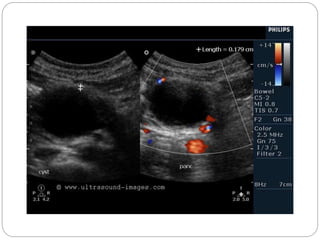

 Ultrasound is more likely to show a

multiloculated cyst with thin septations

than a simple cyst.

Mesenteric cyst.

CT demonstrating a large left-sided cystic

abdominal mass with compression of the left kidney.

Ultrasound showed multiple fine septations within the cyst

Lymphangioma has enhancing septa. Unlike in cystic peritoneal

metastases, ascites is not a feature of lymphangioma.

When you see a septated cystic lesion without ascites the most likely

diagnosis is a lymphangioma